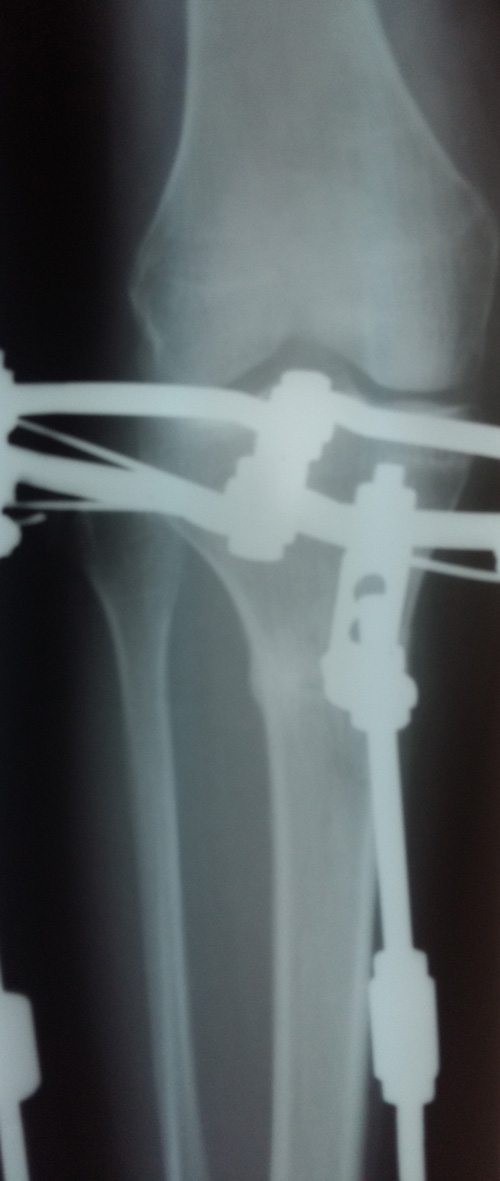

Рентген в 81 день с момента операции.

Здравствуйте, Соломея! По рентгену, у Вас всё отлично! В 90 дней возможно снятие аппаратов. Натаптывайте интенсивно ножки все эти дни, но без фанатизма(ведь когда я Вам говорю больше ходите- это значит, что при физ нагрузке быстрее разрастается костная ткань - вырабатывается, наступает сращение) лучше приехать и остаться у нас в клинике до снятия аппаратов. Один раз можно пожертвовать временем, расстоянием и средствами ради благополучия и отличного результата! Ножки мы исправляем один раз и навсегда!